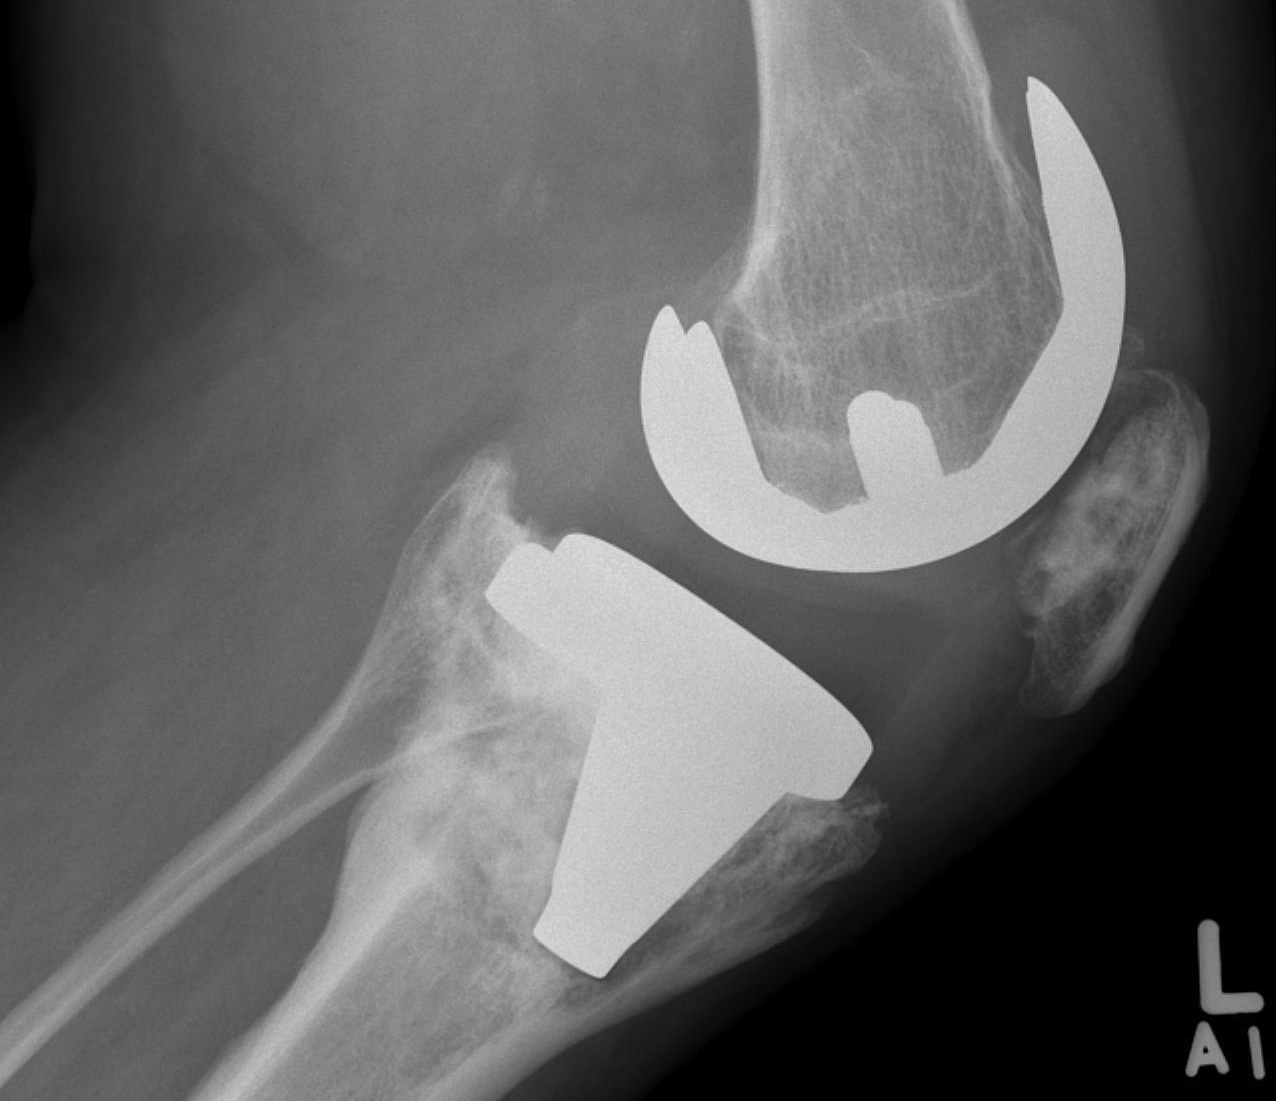

AORI / Andersen Orthopedic Research Institute

T Tibial F Femoral

2. Damaged Metaphyseal

B. Both Condyles

2. Damaged Metaphysis

B Both

Management

A. Cement < 1cm

B. Augments < 2cm

C. Bone graft